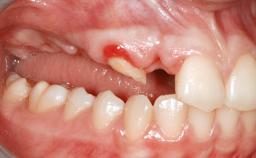

An 18-year-old man was referred for implant therapy in the posterior mandible to the Department of Oral Surgery and Stomatology (University of Bern, Switzerland). He was healthy and did not smoke. Tooth 35 was congenitally missing, involving a single-tooth edentulous space that offered an adequate mesiodistal dimension for implant placement but exhibited a typical pattern of buccal flattening. A panoramic radiograph was obtained, which revealed a sufficient vertical bone height above the mandibular canal and a normal bone structure in the edentulous area.

Bone Volume Deficient horizontally, requiring prior grafting